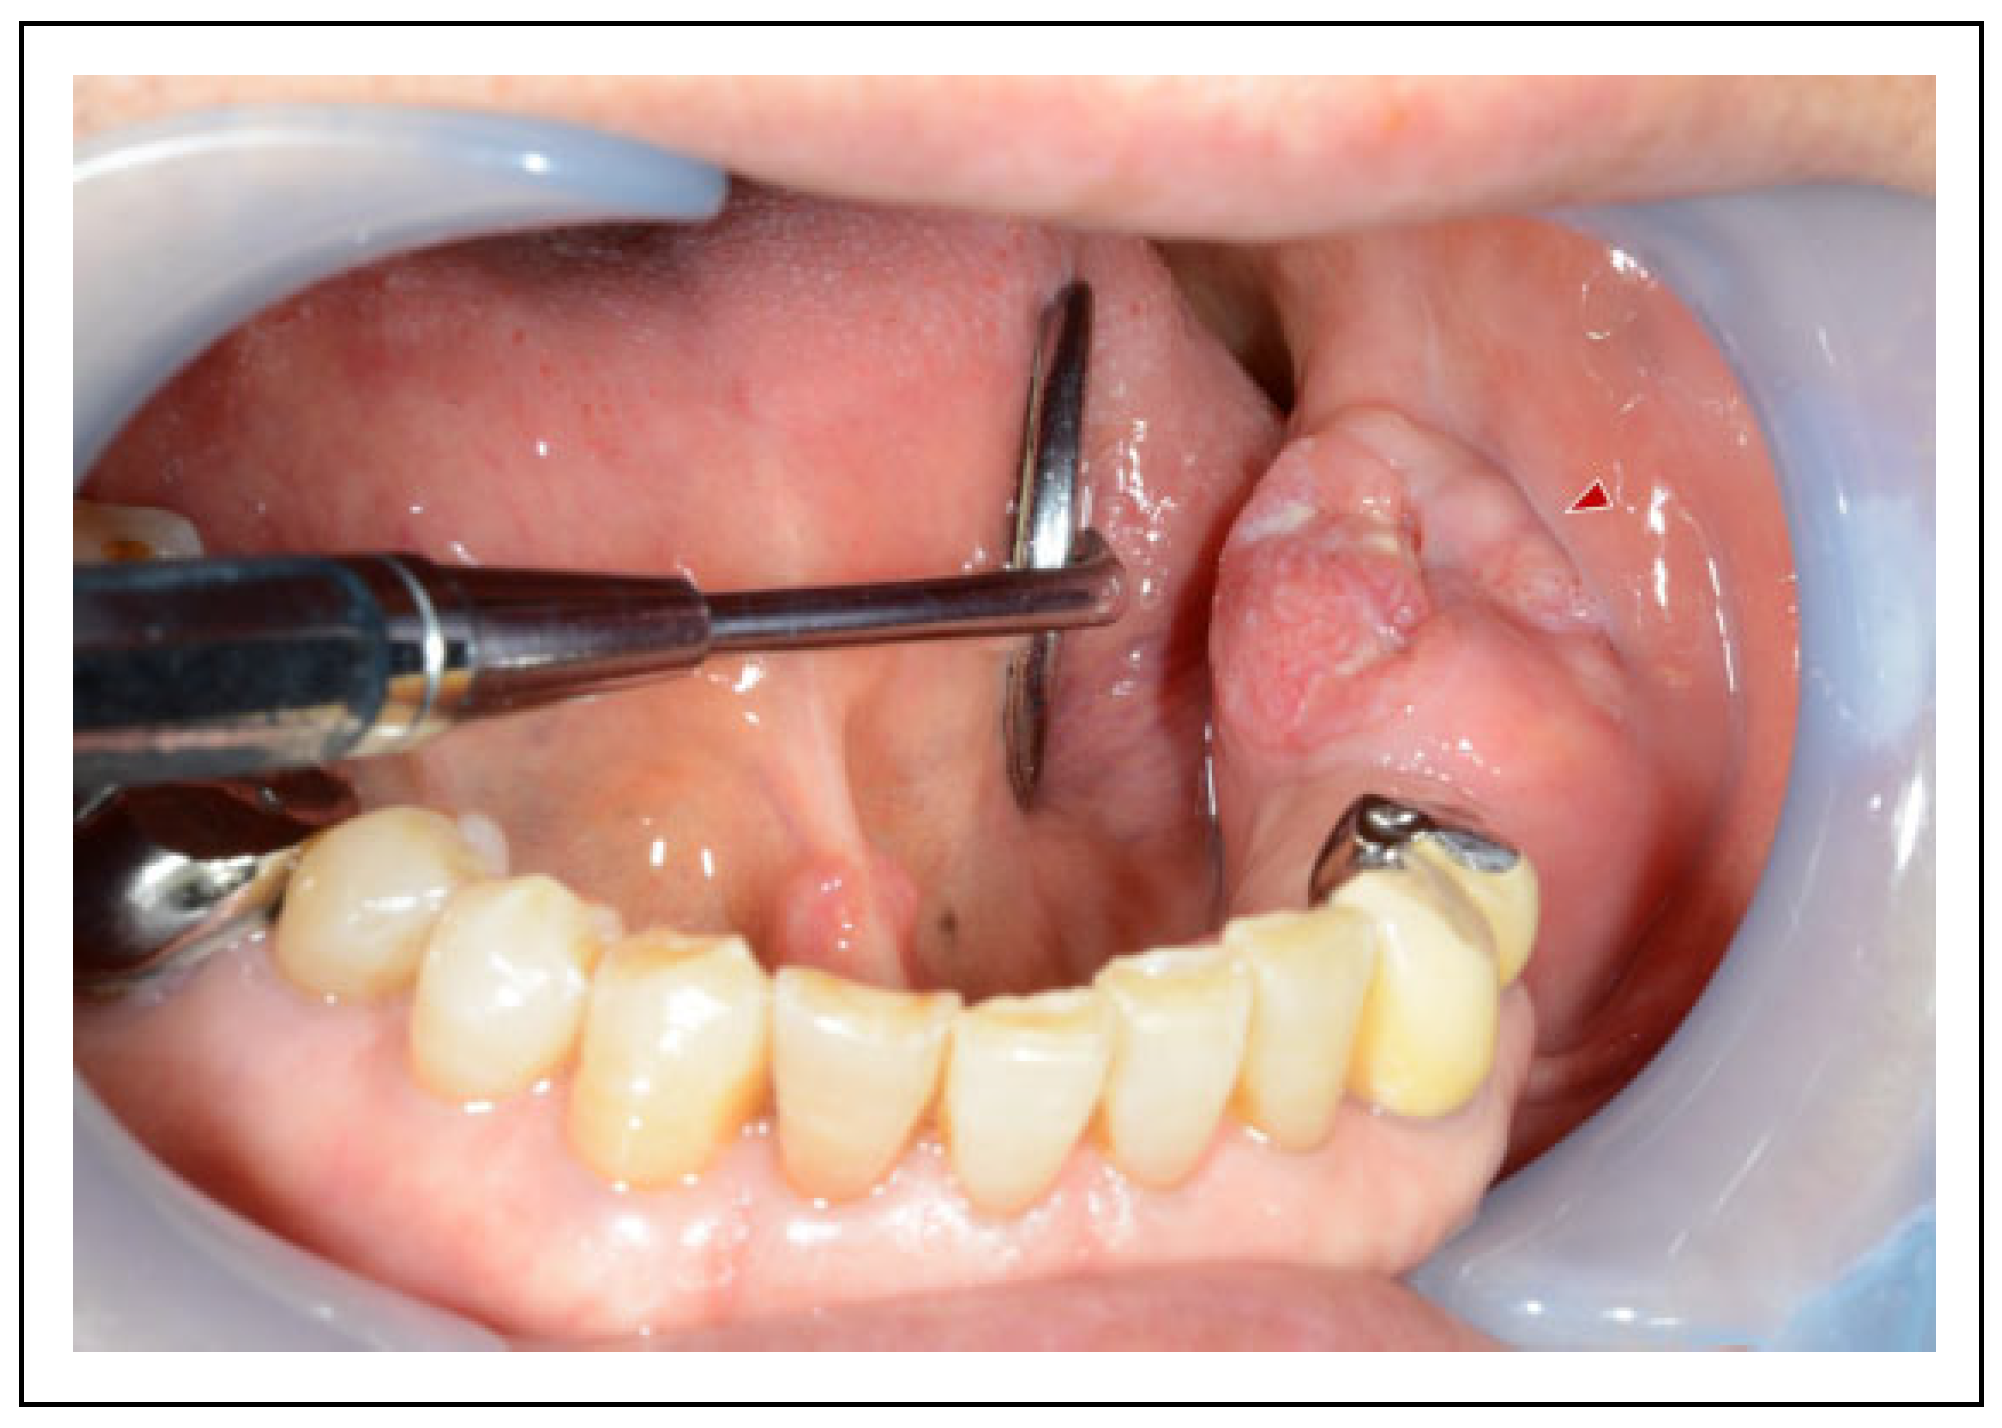

Case Presentation

Surgical Procedure